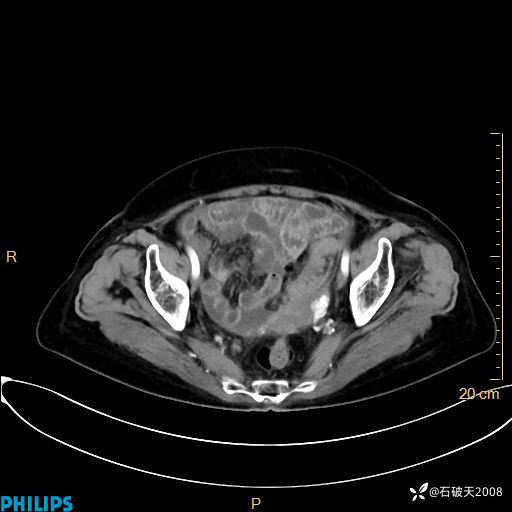

MIP